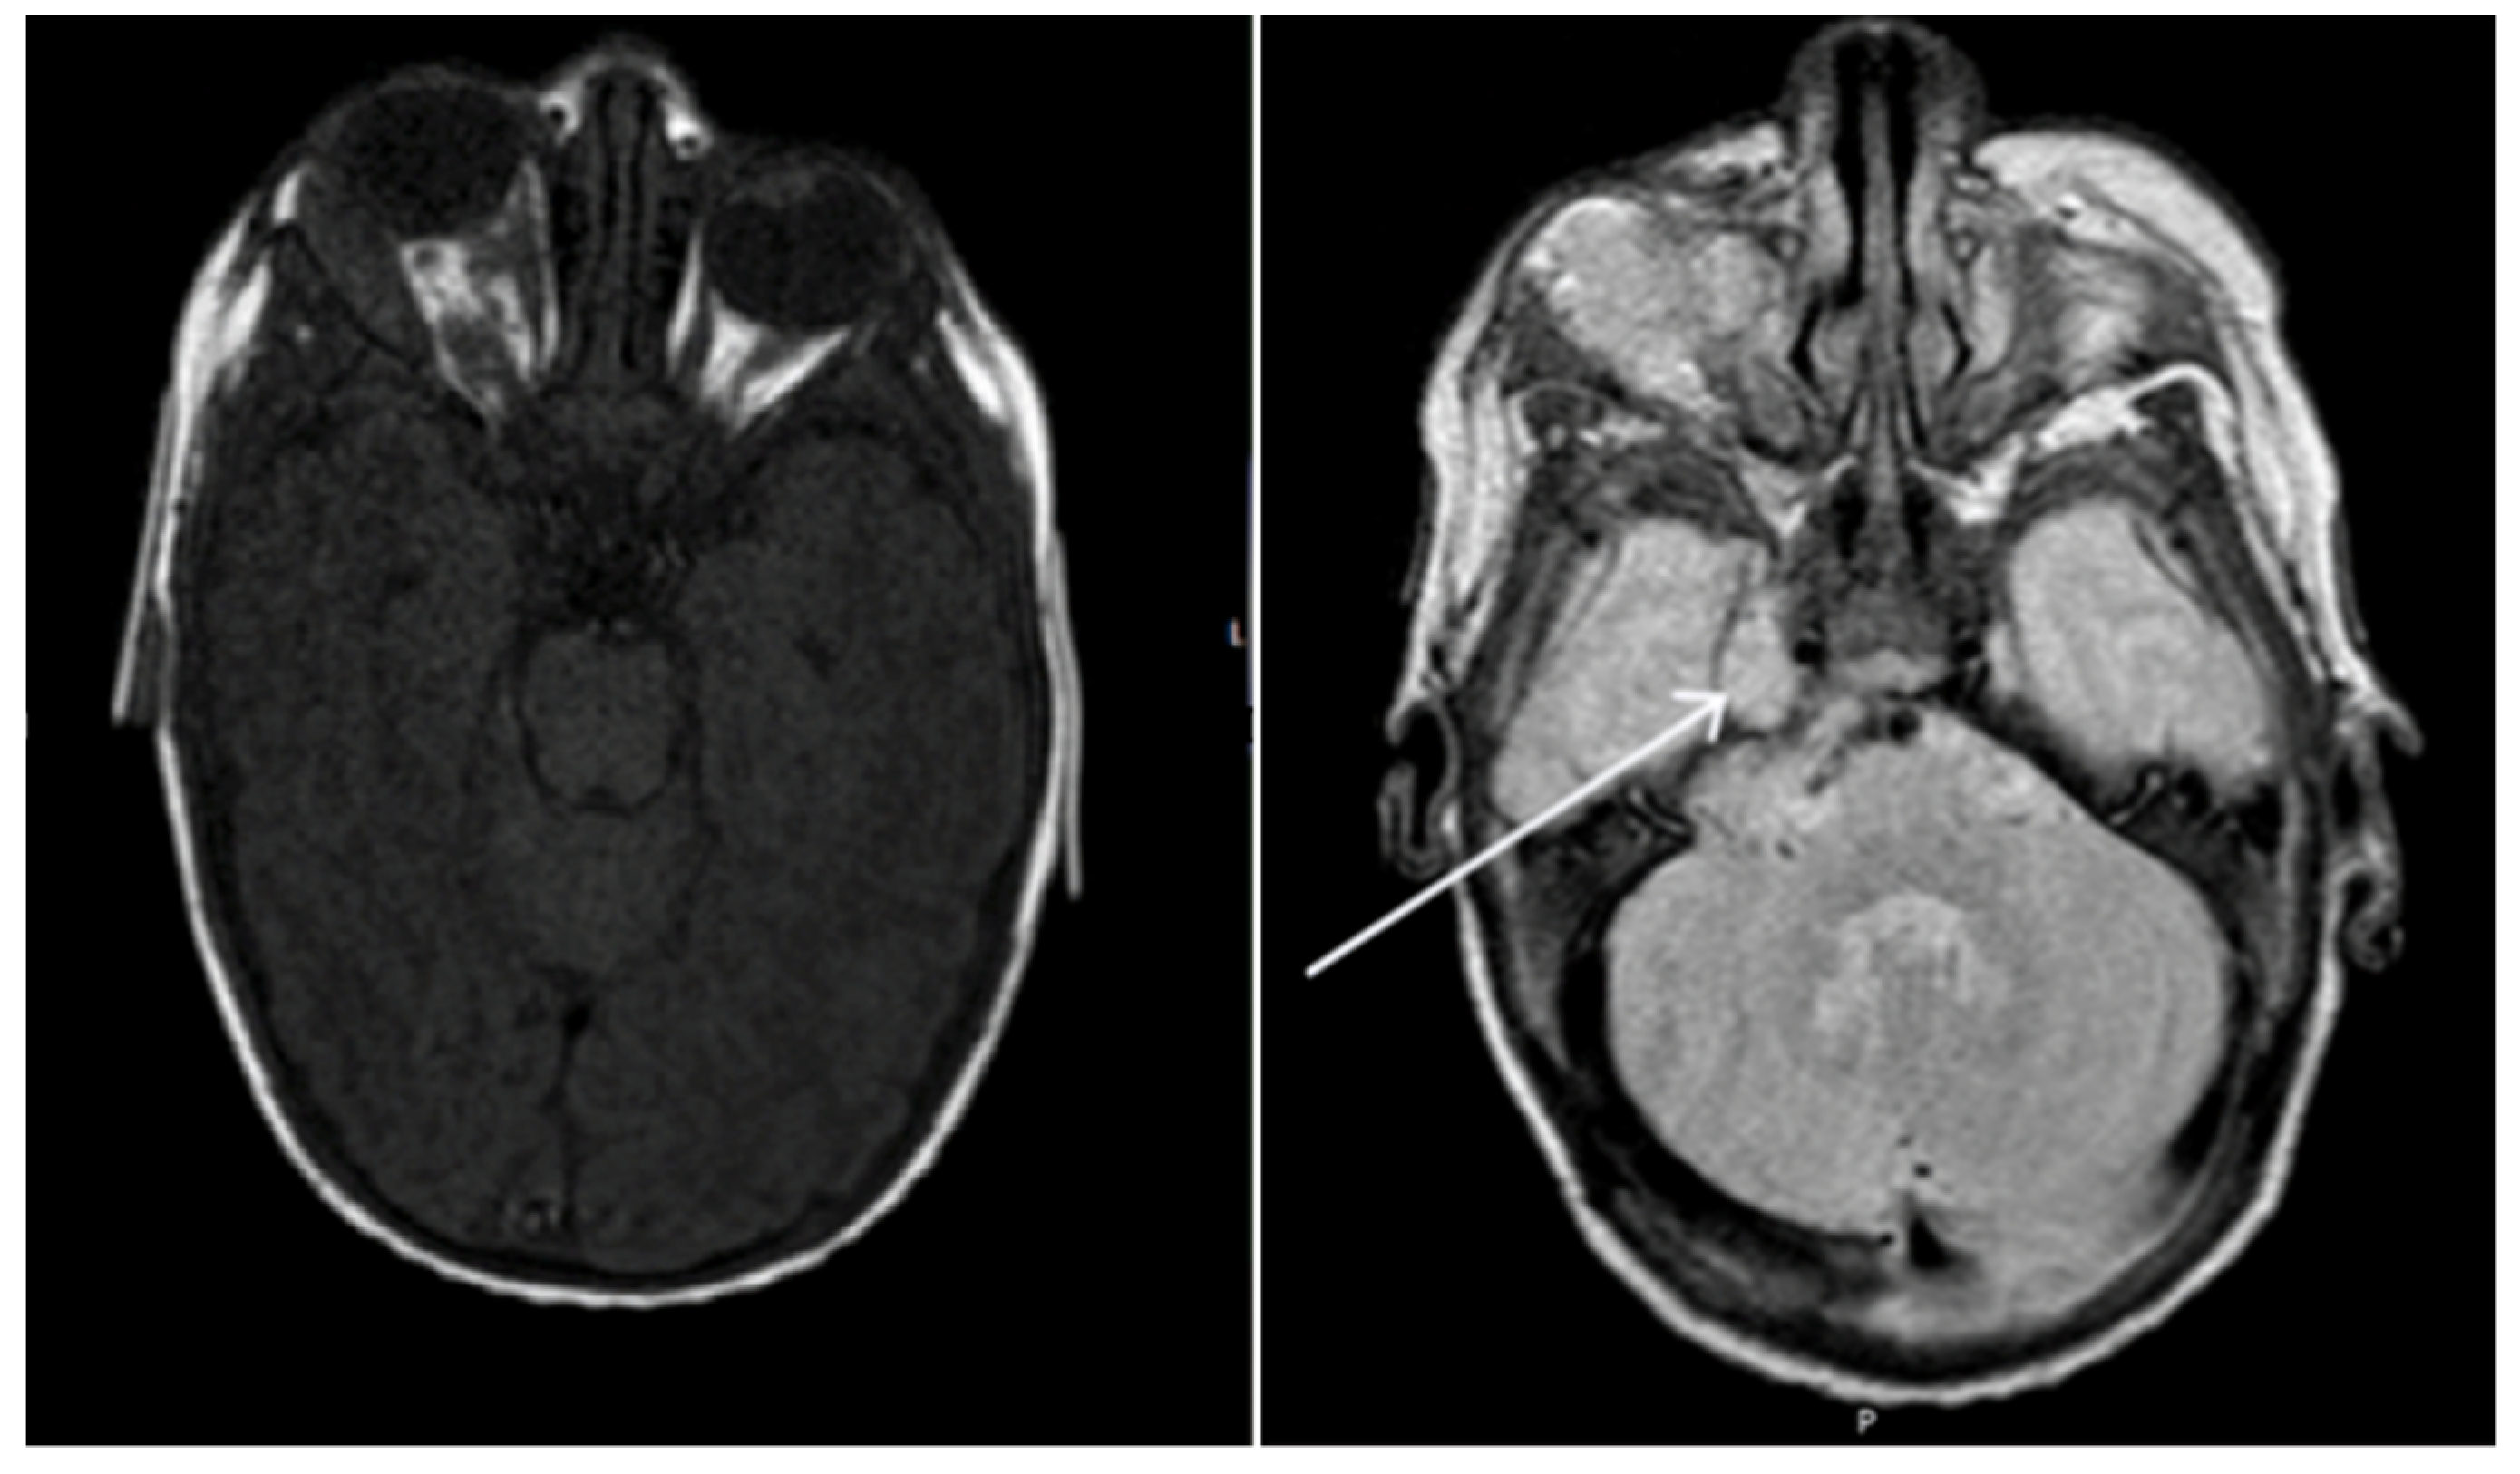

| Naughton et al., 2020 (this paper) | 6 weeks, female | Right CNVII palsy | Right orbit, right CPA and Meckel’s cave | Oral propranolol and topical timolol maleate 0.5% | Resolution |